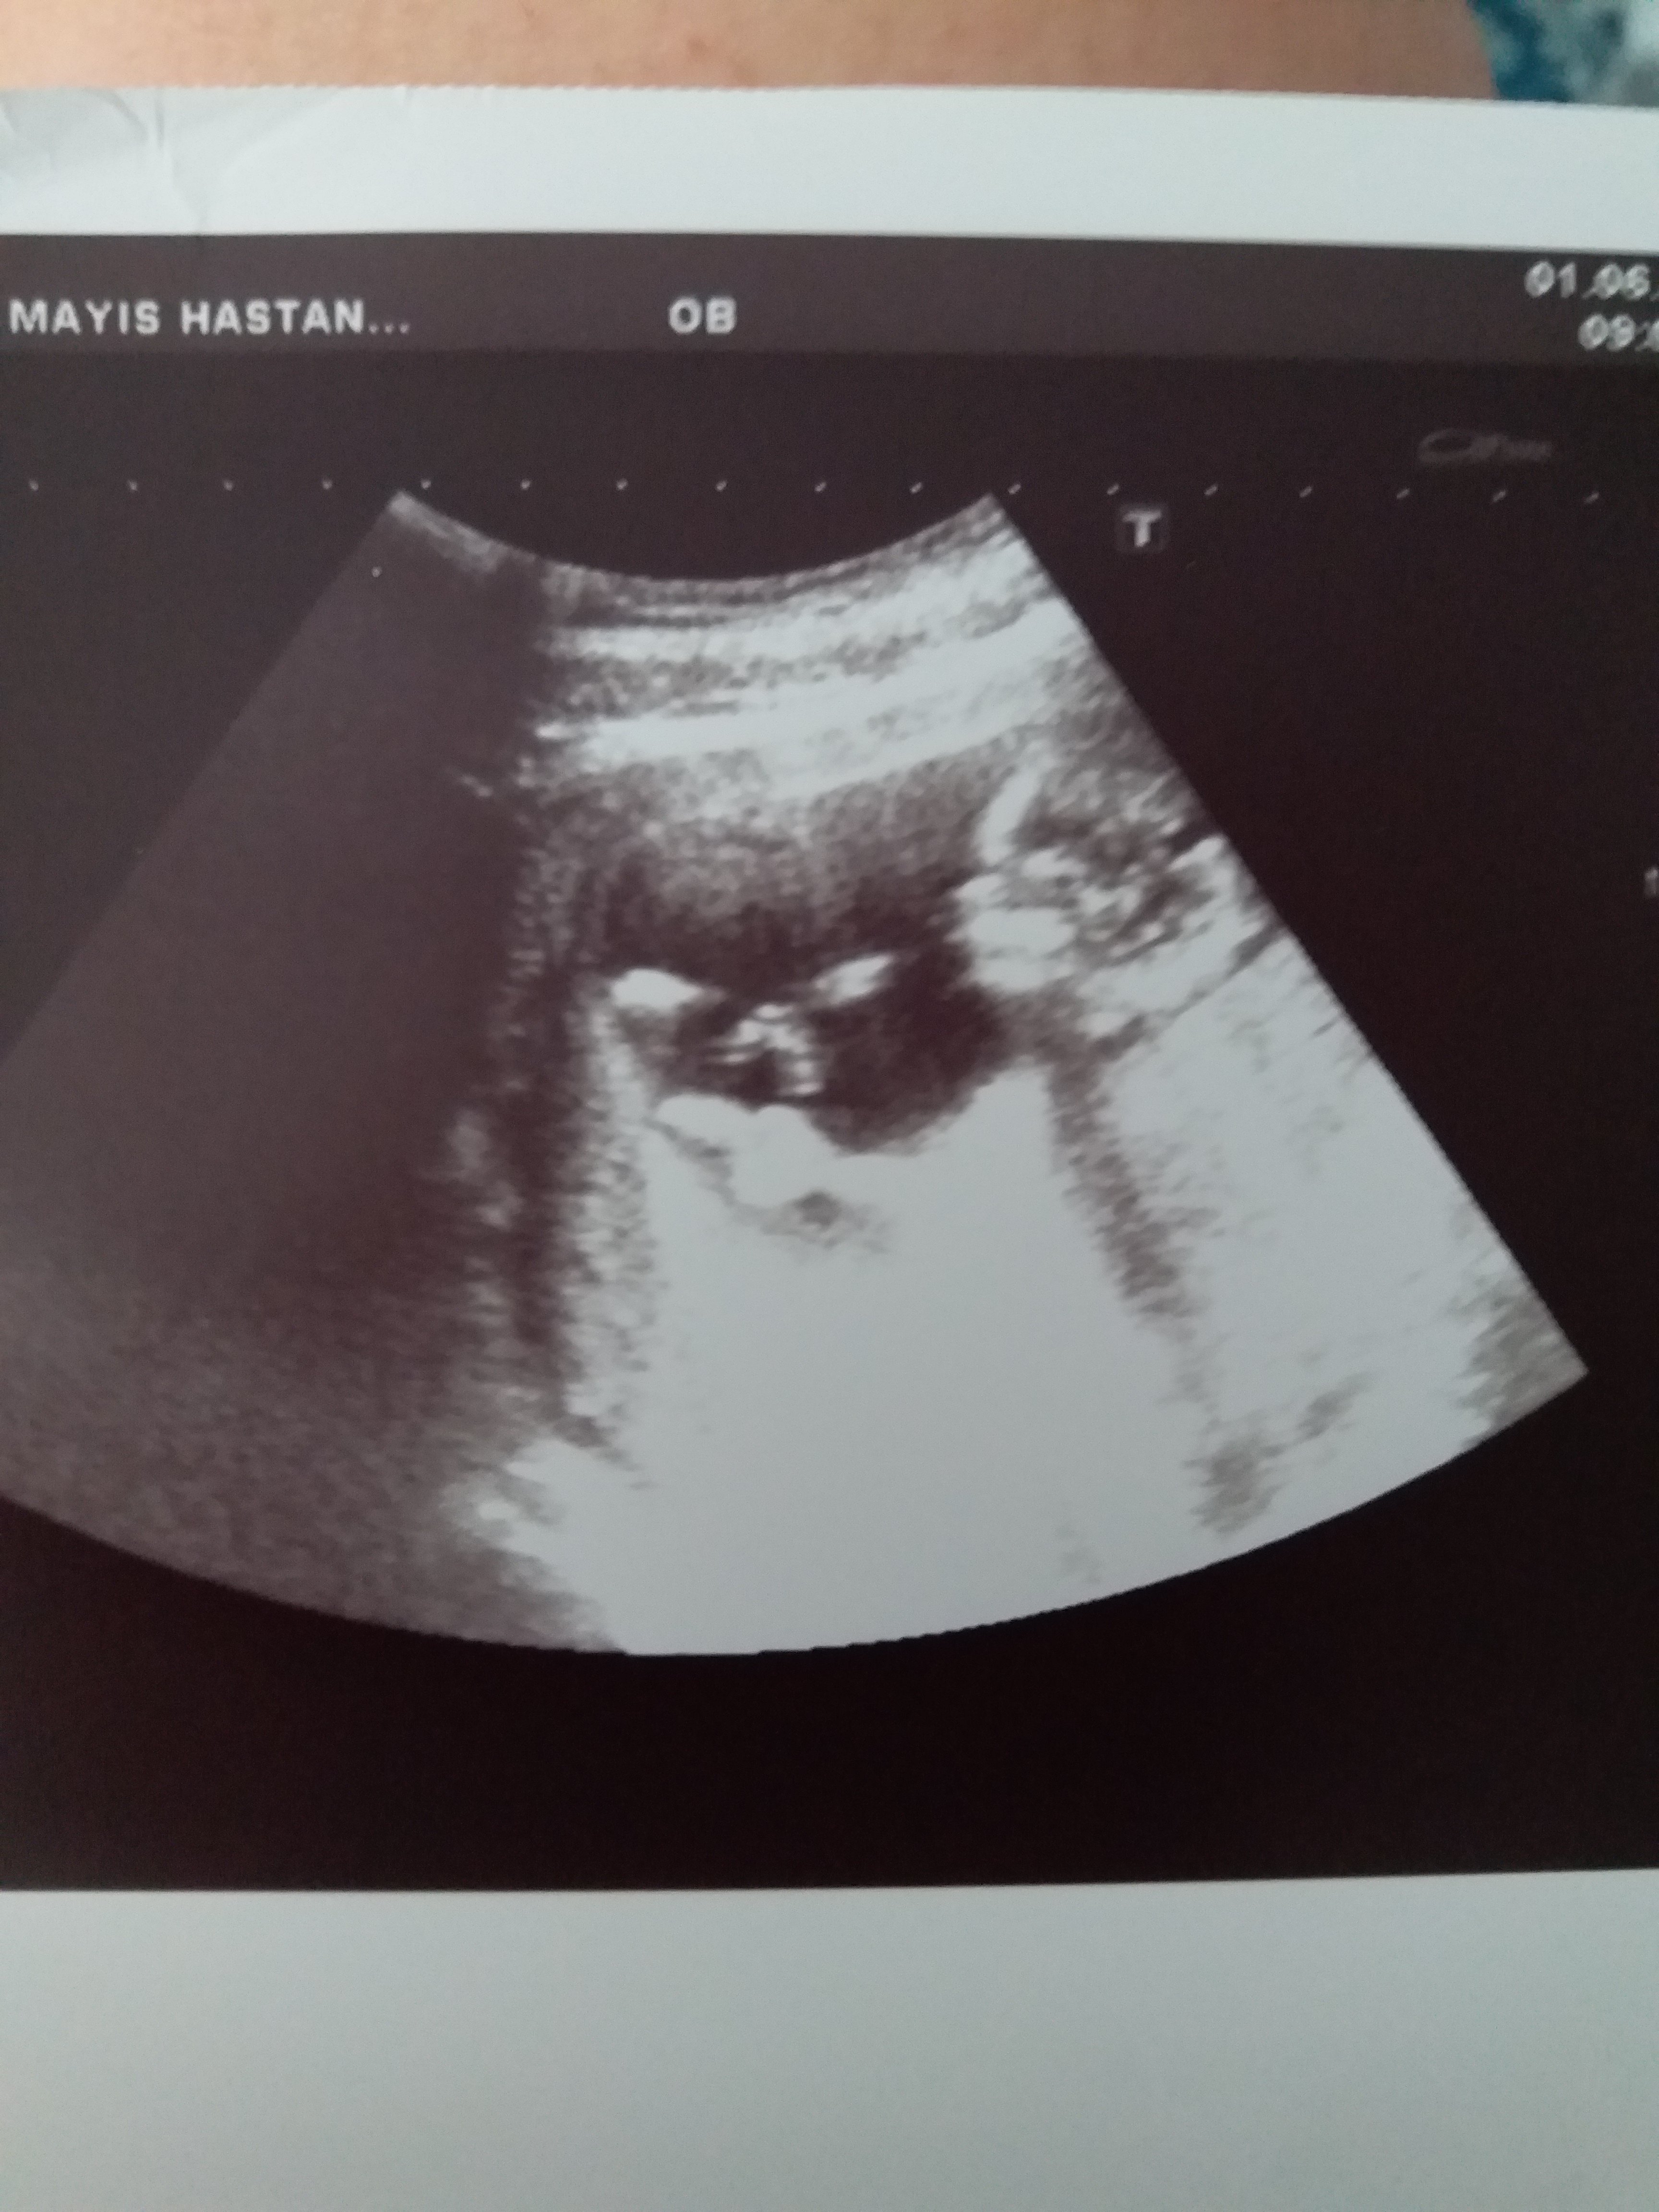

Nub cinsiyet tahmini tutanlar beni de değerlendirir misiniz lütfen ?

Sizce cinsiyet nedir ya bu hafta tekrar gittim doktora net konuşmadı 12 haftadayız lütfen bilen Allah rızası için yardımcı olsun

Yüzde 52 erkek demişti ama değişebilir demişti